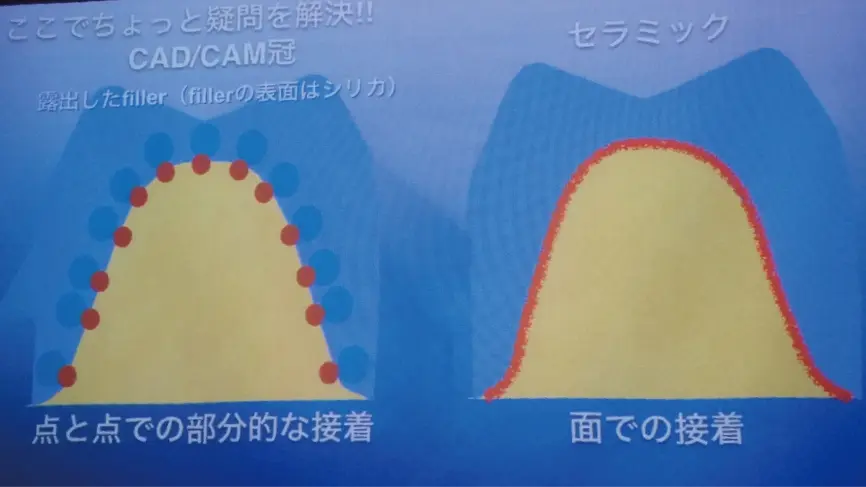

実は、保険適用のCAD/CAM冠(白い樹脂)も

歯と完璧に接着することはありません。

歯と面で完璧に接着するのは

セラミックだけなんです。

また、論文では小さな被せ(部分被覆管)は大きな被せ(全部被覆管)よりも長持ちすることが証明されています。

保険の樹脂は歯と密着する面が少ないため大きな被せにする必要がある一方、セラミックは歯と密着する面が大きく小さな被せでも固定できます。その点でも、セラミックの被せ物は優れていると言えるでしょう。